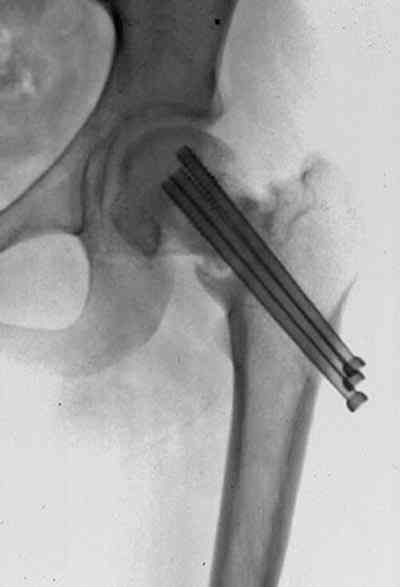

После закрытой репозиции фиксацию проводят:

-параллельными шурупами в форме “V” 6.5, 7.0 или 7.3 мм в зависимости от диаметра шейки

- каннюлированными легче и механически лучше из-за трубчатости шурупа

-желательно титановыми для оценки сращения в будущем с помощью МРТ

-два сверху для закрытия варуса, спереди и сзади шейки и один в нижнем

отделе шейки, в редких случаях 4 в положении diamond или ромб

- концы шурупов довести до эпихондральной зоны, в зависимости от перелома длина резьбы шурупов 16 или 32 мм

-расположение шурупов дальше от центра шейки и ближе к кортексу -под углом 130 градусов, введение под большим углом или ниже малого вертеля может осложниться субтрохантерными переломами из-за ослабления латерального кортекса, поэтому внизу рекомендуется только один шуруп - при явном остеопорозе применяются шайбы